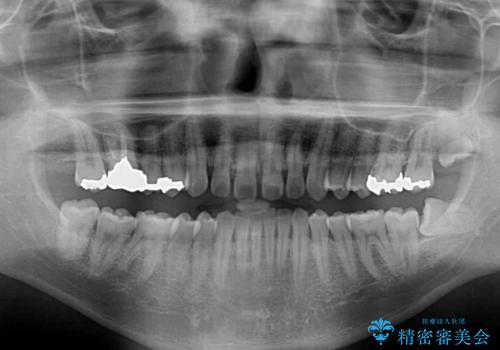

- 咬み合わせにより上顎正中に隙間ができているとのことで来院された患者様です。

インビザラインは自己管理が煩わしく、表側のワイヤー装置は目立つので避けたいとのことで、上顎だけが裏側装置のハーフリンガルにて矯正治療を行うこととしました。